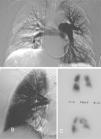

Se evaluó clínicamente a todos los pacientes en la consulta de la Unidad de Cirugía Mínimamente Invasiva Guiada por Imagen al cabo de 1; 3; 6, y 12 meses, y posteriormente cada año, mediante la valoración funcional según la clasificación de la NYHA, estudio gammagráfico y ecografía Doppler cardíaca para valorar las alteraciones sobre cavidades derechas, y estudio de presiones indirectas. No se realizó test de la marcha de 6min. La valoración gammagráfica se basó en la extensión y el número de segmentos mal perfundidos que no concordaban con el examen previo al tratamiento, pero no se cuantificó numéricamente. En el control llevado a cabo a los 3 meses, coincidiendo con la recuperación del filtro en la vena cava inferior, se efectuó una angiografía pulmonar (fig. 4).

Seguimiento a los 3 meses, coincidiendo con la retirada del filtro, de una paciente asintomática con clase funcional I de la clasificación de la New York Heart Association y presión arterial pulmonar media de 27mmHg. A: arteriografía de arterias pulmonares, que muestra prótesis metálica permeable y ramas lobulares derechas. B: angiografía en proyección oblicua anterior derecha, donde se observan prótesis metálica y ramas permeables, así como buena perfusión distal. C: gammagrafía de perfusión, que muestra aceptable distribución del isótopo, con defectos de perfusión segmentarios bilaterales.

Durante el seguimiento, que se realizó en la consulta de la Unidad de Cirugía Mínimamente Invasiva en coordinación con otras unidades clínicas, se observaron una mejoría clínica objetiva en la clasificación de la NYHA, mejoría hemodinámica evidenciada en la ecografía Doppler y mejoría morfológica objetivada en la arteriografía y en la gammagrafía pulmonar de perfusión (tabla III). La media de seguimiento fue de 18,7 meses (rango: 11-36). Seis pacientes experimentaron una franca mejoría clínica, rebajando su grado en la clasificación de la NYHA. La presión arterial pulmonar media medida por ecografía Doppler descendió a 24mmHg, lo que supuso una mejora significativa de 25,4mmHg (p < 0,005). La gammagrafía pulmonar fue normal en 2 pacientes; en 3 mostró pequeños defectos de perfusión difusos, y en 2 los defectos fueron de mayor entidad. En la arteriografía pulmonar realizada a los 3 meses, en 6 pacientes se observó una franca mejoría, como se muestra en la figura 4. A los 3 meses se retiraron por vía yugular 6 de los 7 filtros sin complicaciones. Uno requirió una fuerza mayor de la normal por encontrarse el garfio superior incluido en la pared de la vena cava. En un paciente no se retiró el filtro por presentar un nuevo episodio de trombosis venosa profunda y rechazar su retirada.